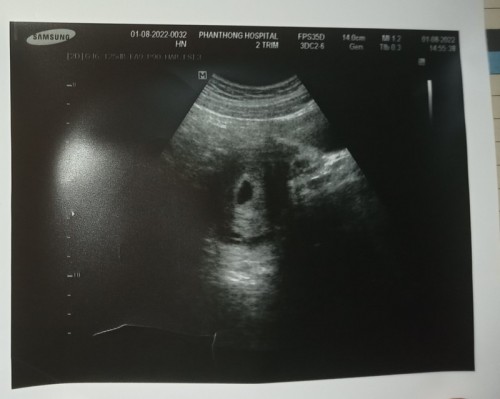

ภาพนี้ 10 w ค่ะ ไปซาวด์ครั้งแรกตอน 6 วีค เห็นน้องเป็นก้อนเล็กๆค่ะ ไม่ต้องกังวลนะคะ บำรุงเยอะๆเดี๋ยวได้เจอน้องค่ะ ตอนนี้แม่บ้านนี้อายุครรภ์ 16 w ค่ะ

ไปซาวด์ครั้งแรก 5 w ไม่เจอเจอแต่ถึงตั้งครรภ์ วันนี้ไปอีกรอบเจอ 10 Wค่ะ พึ่งไปซาวด์มาวันนี้เลย